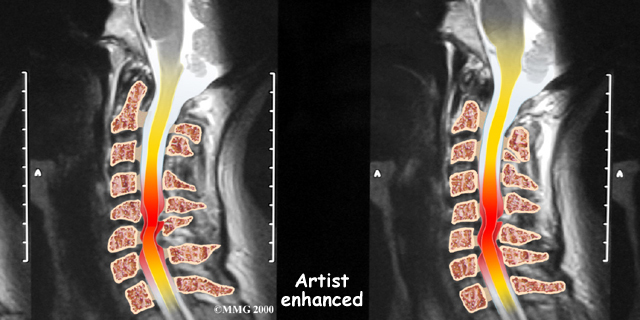

If more information is needed, your doctor may order a magnetic resonance imaging (MRI) scan. The MRI machine uses magnetic waves rather than X-rays to show the soft tissues of the body. This test gives a clear picture of the spinal cord and can show where it is being squeezed. This machine creates pictures that look like slices of the area your doctor is interested in. The test does not require any special dye or a needle.

Soft Tissues